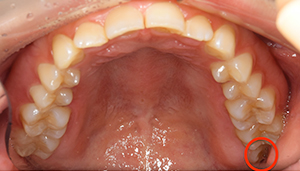

親知らずが虫歯になっている症例

- 抜歯前の口腔内写真

| 治療方針 | 初診時に親知らずの虫歯を確認しました。 先に別の部位の治療をしていましたが、痛みが出てきたため抜歯を行うこととなりました。 |

| 特記事項 | 抜歯をする前にCTを撮影をし、下歯槽神経との位置を確認した上で抜歯を行いました。 |

| 担当者所見 | 初診のご来院時から、すでに虫歯が大きく進行していました。 ご来院時にお痛みはなかったものの、大きい虫歯でしたので、いつ痛みだしてもおかしくない状態でした。 麻酔が効きづらかったため抜歯に時間を要しましたが、根が折れることなく無事に抜けました。 |